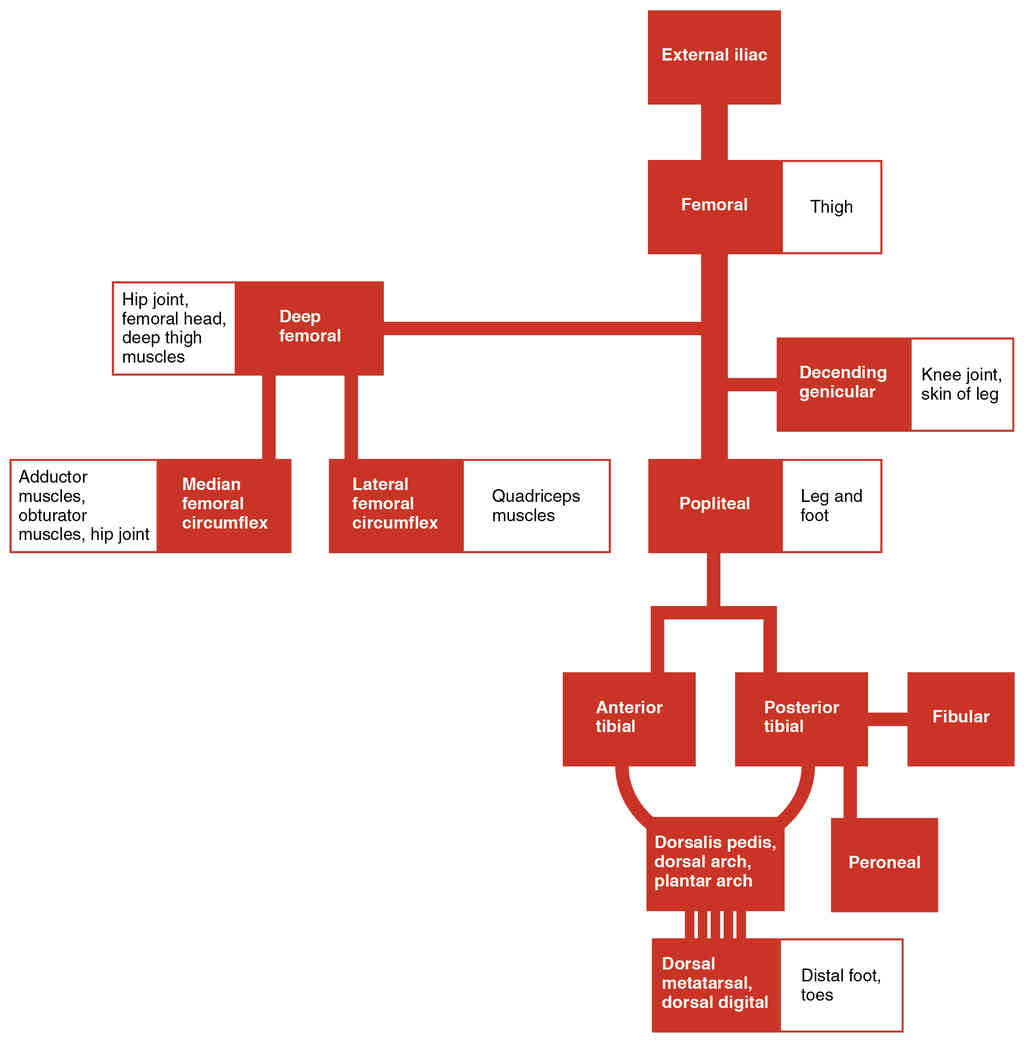

This page is under construction. For now, it is just a resource of the images found in the OpenStax Anatomy and Physiology Handbook. It wil slowly change into a revision tool. Each slide has a number. Use this to refer to the slide. When completed, it will have an unlabelled section, with labelled slides in parallel. On the unlabelled slides, write your answer and use the labelled slide to assess yourself. Keep track by also noting the number on each slide. Improvement at each attempt is important, more so than full marks on a first attempt.